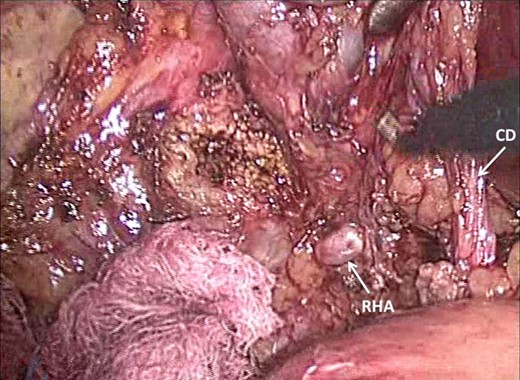

A laparoscopic completion cholecystectomy was performed. There were multiple dense adhesions that precluded visualization of the gallbladder remnant (Fig. 2). Meticulous dissection with cautery attached to ‘hot scissors’ eventually presented the gallbladder remnant (Fig. 3). Scarring at Calot's triangle prevented retrograde dissection, so the ‘dome down’ technique was used to identify cystic duct (CD) (Fig. 4) and right hepatic structures at the floor of an open-type Rouviere's sulcus (Fig. 5). Intraoperative cholangiography was performed via the CD using a 5Fr infant feeding (Fig. 6) and confirmed that: this structure was the CD, the extra-hepatic biliary tree was normal and there were no stones in the CBD (Fig. 7). At this point, the CD and artery were ligated and ‘hot scissors’ were used to separate the gallbladder remnant from the liver bed. This patient recovered uneventfully and remained asymptomatic 2 years later.

Dissection has presented Rouviere's sulcus (open-type) with the right hepatic artery (RHA) visible superficially. The close relationship to the CD in Calot's triangle is demonstrated.